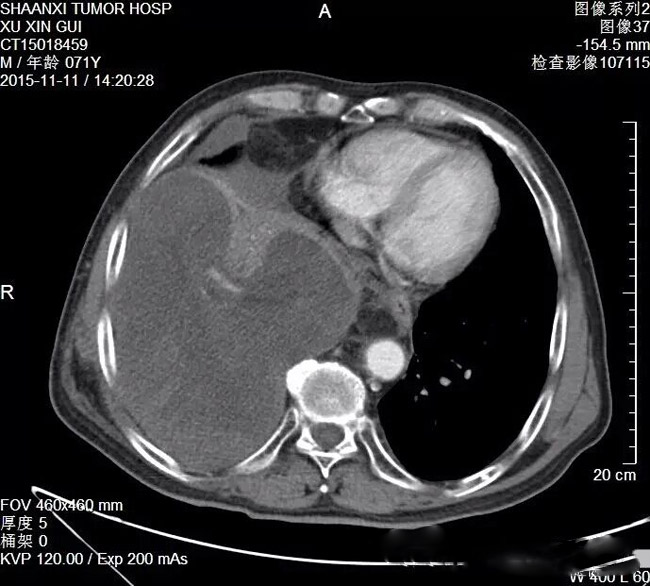

胸外科成功切除一例胸腔巨大复发脂肪肉瘤